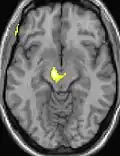

| Diese Kernspintomographie mit eingezeichneter Morphometrie zeigt einen höheren Anteil an Grauer Substanz im Hypothalamus rechts (im Bild links) | ||

Die Positronen-Emissions-Tomographie (PET)-Darstellungen oben zeigen die funktionellen Daten, also die Bereiche, welche bei Schmerzen Aktivität aufweisen, im Vergleich zum Aussehen bei einem schmerzfreien Intervall. Man sieht die sog. Schmerzmatrix, die immer bei Schmerz aktiviert ist und das Areal in der Mitte (in allen drei Ebenen), welches spezifisch im Cluster-Kopfschmerz aktiviert ist. Die VBM Bilder unten zeigen die strukturellen Daten. Hier wird untersucht, ob die Gehirne von Cluster-Kopfschmerz-Patienten anders sind als die Gehirne von Menschen ohne Kopfschmerzen. Nur ein Areal ist anders, da es mehr Graue Substanz enthält: Dieses entspricht dem oben gezeigten funktionellen Areal. Es handelt sich um den Hypothalamus. Dort wird unter anderem der Schlaf-Wach-Rhythmus generiert. Man vermutet daher den Motor des Cluster-Kopfschmerzes im Hypothalamus.[27][28] Mit der 1H-Magnetresonanzspektroskopie konnten auch biochemische Unterschiede zwischen dem Hypothalamus gesunder Menschen und dem Hypothalamus von Cluster-Kopfschmerz-Patienten nachgewiesen werden.[29][30]

Nach Forschungsergebnissen[31] aus dem Oktober 2014 wird aber angenommen, dass die Krankheit eher von einer Netzwerkstörung und nicht nur durch den Hypothalamus verursacht wird. Bei Patienten mit Cluster-Kopfschmerz wurden im Vergleich zu gesunden Individuen Veränderungen der grauen Substanz, in den Bereichen der Schmerzverarbeitung und darüber hinaus, identifiziert. Diese Veränderungen der grauen Substanz unterschieden sich signifikant bei chronischem und episodischem Cluster-Kopfschmerz sowie innerhalb und außerhalb der Episode. Ein Rückgang der grauen Substanz wurde vorwiegend bei chronischem Cluster-Kopfschmerz beobachtet, während episodischer Cluster-Kopfschmerz ein komplexeres und teilweise entgegengesetztes Muster zeigte. Diese Dynamik reflektiert wahrscheinlich die Anpassungsfähigkeit des Gehirns auf wechselnde Reize in Bezug auf kortikale Plastizität und könnte eine Erklärung für die unterschiedlichen Ergebnisse früherer VBM-Studien zu Schmerzen liefern.